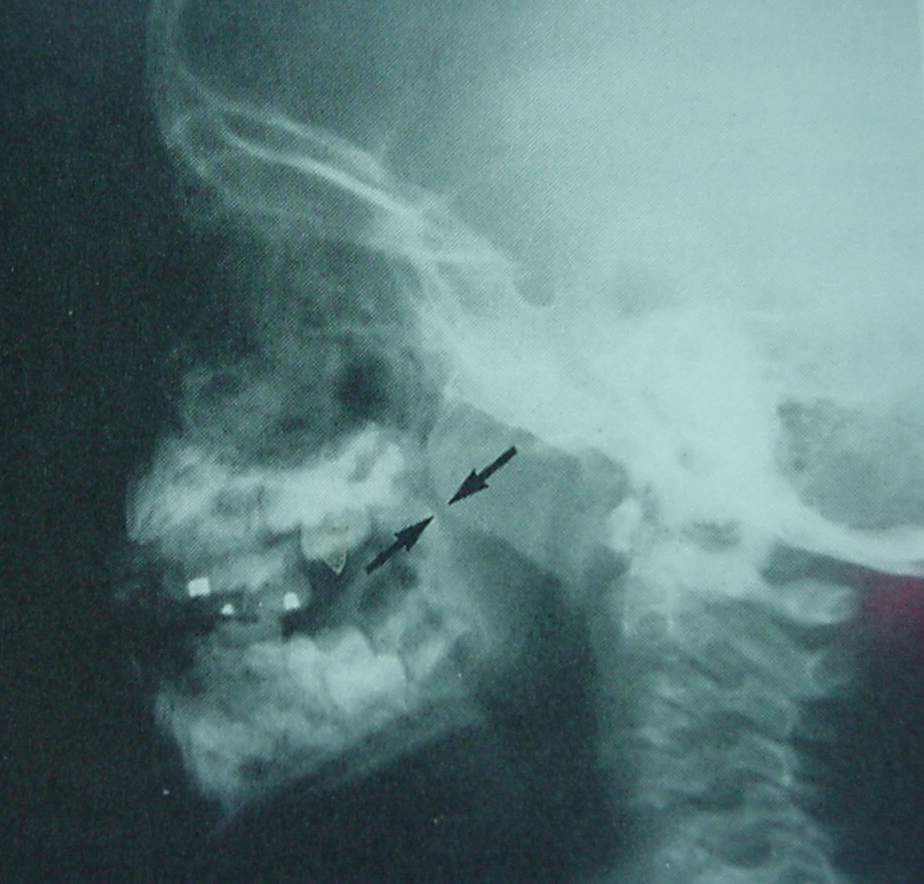

Pharynx and Esophagus Clinical Photos for Static Stations